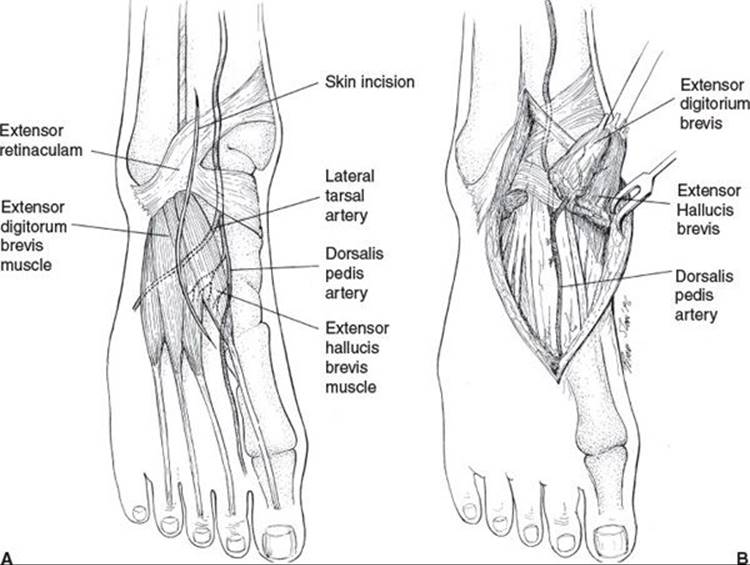

The EDB muscle (Figure 95.8) has disappointingly little bulk but can be used for local defects over the sinus tarsi or lateral calcaneus. The muscle can be rotated either in a limited fashion on its dominant pedicle, the lateral tarsal artery, or in a wider arc if harvested with the dorsalis pedis artery. The flexor digitorum brevis muscle can be used to cover plantar heel defects. Because the muscle bulk is small, it works best if it is used to fill a deep defect that can then be covered with plantar tissue.

FIGURE 95.8. The extensor digitorum brevis muscle is a small muscle based on the lateral tarsal artery that covers small defects over the anterior ankle and sinus tarsi. It can be harvested on its short dominant proximal lateral tarsal artery pedicle. Its reach can be extended by including the dorsalis pedis artery with either antegrade or retrograde flow depending on the location of the wound. (From Attinger C. Soft tissue coverage for lower extremity trauma. Orthop Clin North Am. 1995;26:3, with permission.)